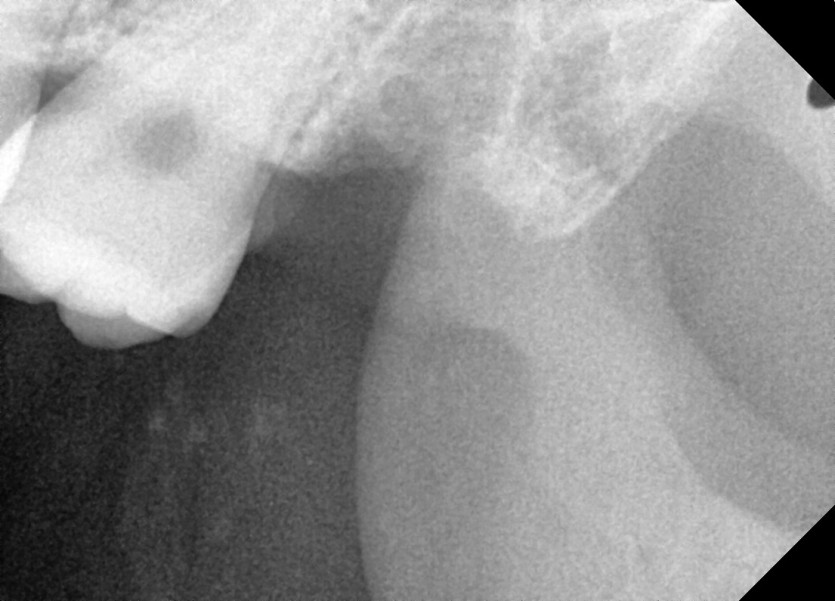

#28, 38 사랑니 발치

구강 외과 전문의가 당일 발치했습니다.